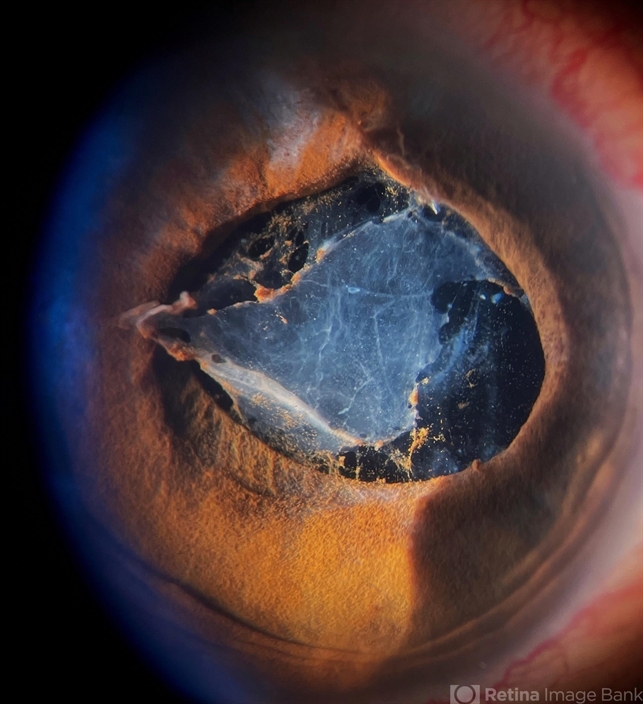

- endophthalmitis, pupillary membranes

- Anterior segment photography of a 54-year-old woman with post phacoemulsification endophthalmitis. She did not improve after first intravitreal antibiotics injection and develop an inflammatory pupillary membrane. After two vitrectomies, and a complete three intravitreal injections scheme, we decided to remove the intraocular lens and capsules.